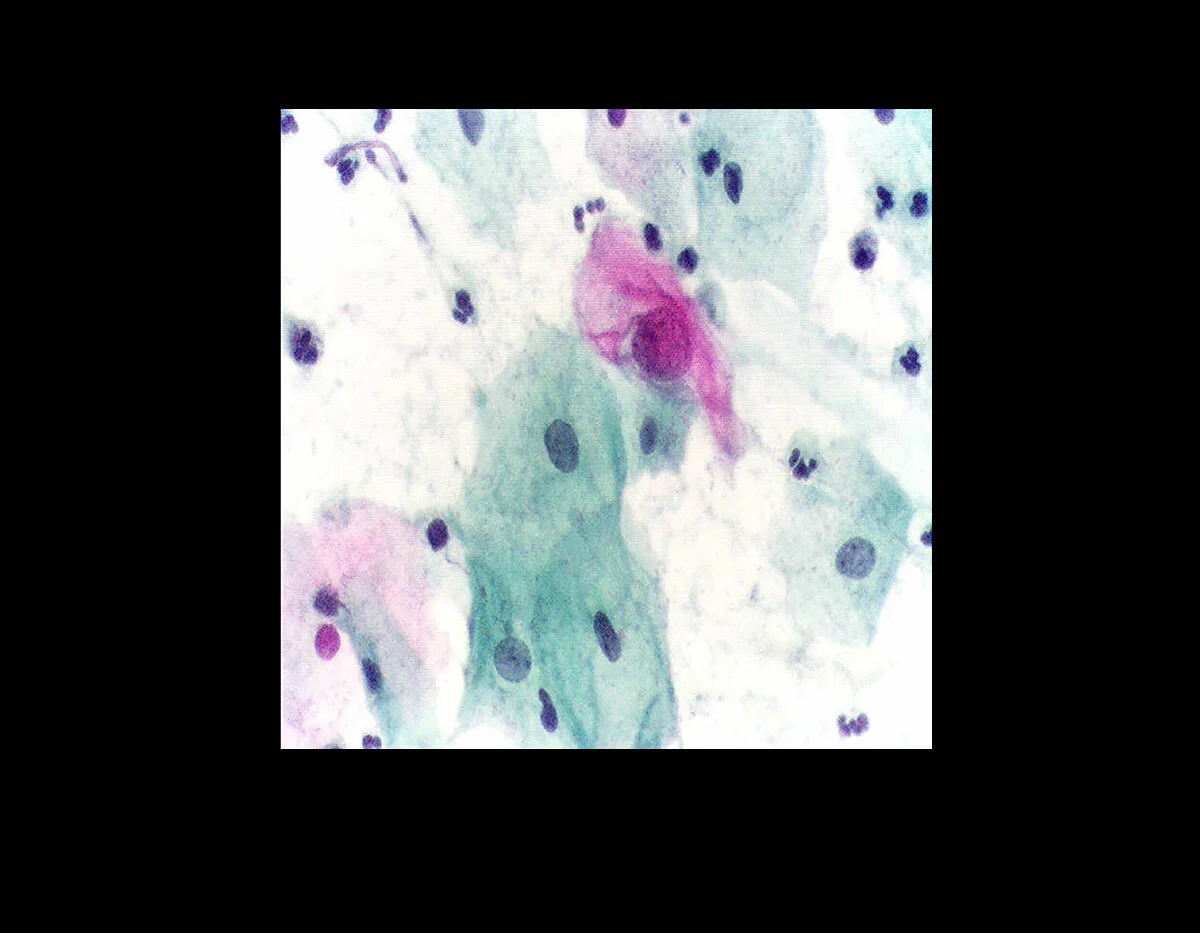

«Η πρώτη παρατήρηση των καρκινικών κυττάρων στο επίχρισμα του τραχήλου της μήτρας μού έδωσε μία από τις μεγαλύτερες συγκινήσεις που έχω βιώσει κατά τη διάρκεια της επιστημονικής σταδιοδρομίας μου». (Γεώργιος Παπανικολάου)

Τα ευρήματα αυτά συνέκρινε με τον ορμονικό προσδιορισμό του ωοθηκικού κύκλου των θηλαστικών στα κολπικά επιχρίσματα. Μελετώντας το υλικό του, διαπίστωσε ότι μεταξύ των κυττάρων υπήρχαν κύτταρα ανώμαλα, που είχαν σχέση με τον καρκίνο του τραχήλου της μήτρας.

Η δεκαετία του 1920 ήταν για αυτόν η περισσότερο δημιουργική. Πραγματοποίησε τις πρώτες κλινικοεργαστηριακές μελέτες για τη διαγνωστική αξία της κυτταρολογικής εξέτασης του κολπικού επιχρίσματος στις γυναίκες.

Η πρωτοποριακή κυτταροδιαγνωστική μέθοδος του Dr. Pap δοκιμάστηκε πρώτα σε φυσιολογικές γυναίκες και έγινε γνωστή ως «Pap smear» (επίχρισμα Παπανικολάου) και «Pap Test» (δοκιμασία Παπανικολάου).

Ακολούθησαν τα πρώτα κλινικά ευρήματα σε καρκινοπαθείς γυναίκες του «Women’s Hospital» της Νέας Υόρκης (1925).

Το 1941 δημοσίευσε στο περιοδικό «American journal» εργασία με τίτλο: «Η διαγνωστική αξία του κολπικού επιχρίσματος στη διάγνωση του καρκίνου του τραχήλου της μήτρας», στην οποία τονιζόταν η αναγκαιότητα εφαρμογής της μεθόδου στο σύνολο των γυναικών για τη διάγνωση σε πρώιμο ιάσιμο στάδιο του καρκίνου του τραχήλου της μήτρας.

Επίσης περιέγραφε τον τρόπο συλλογής των κυττάρων, τη χρώση και τα μορφολογικά χαρακτηριστικά στα οποία στηρίζεται η διάγνωση.